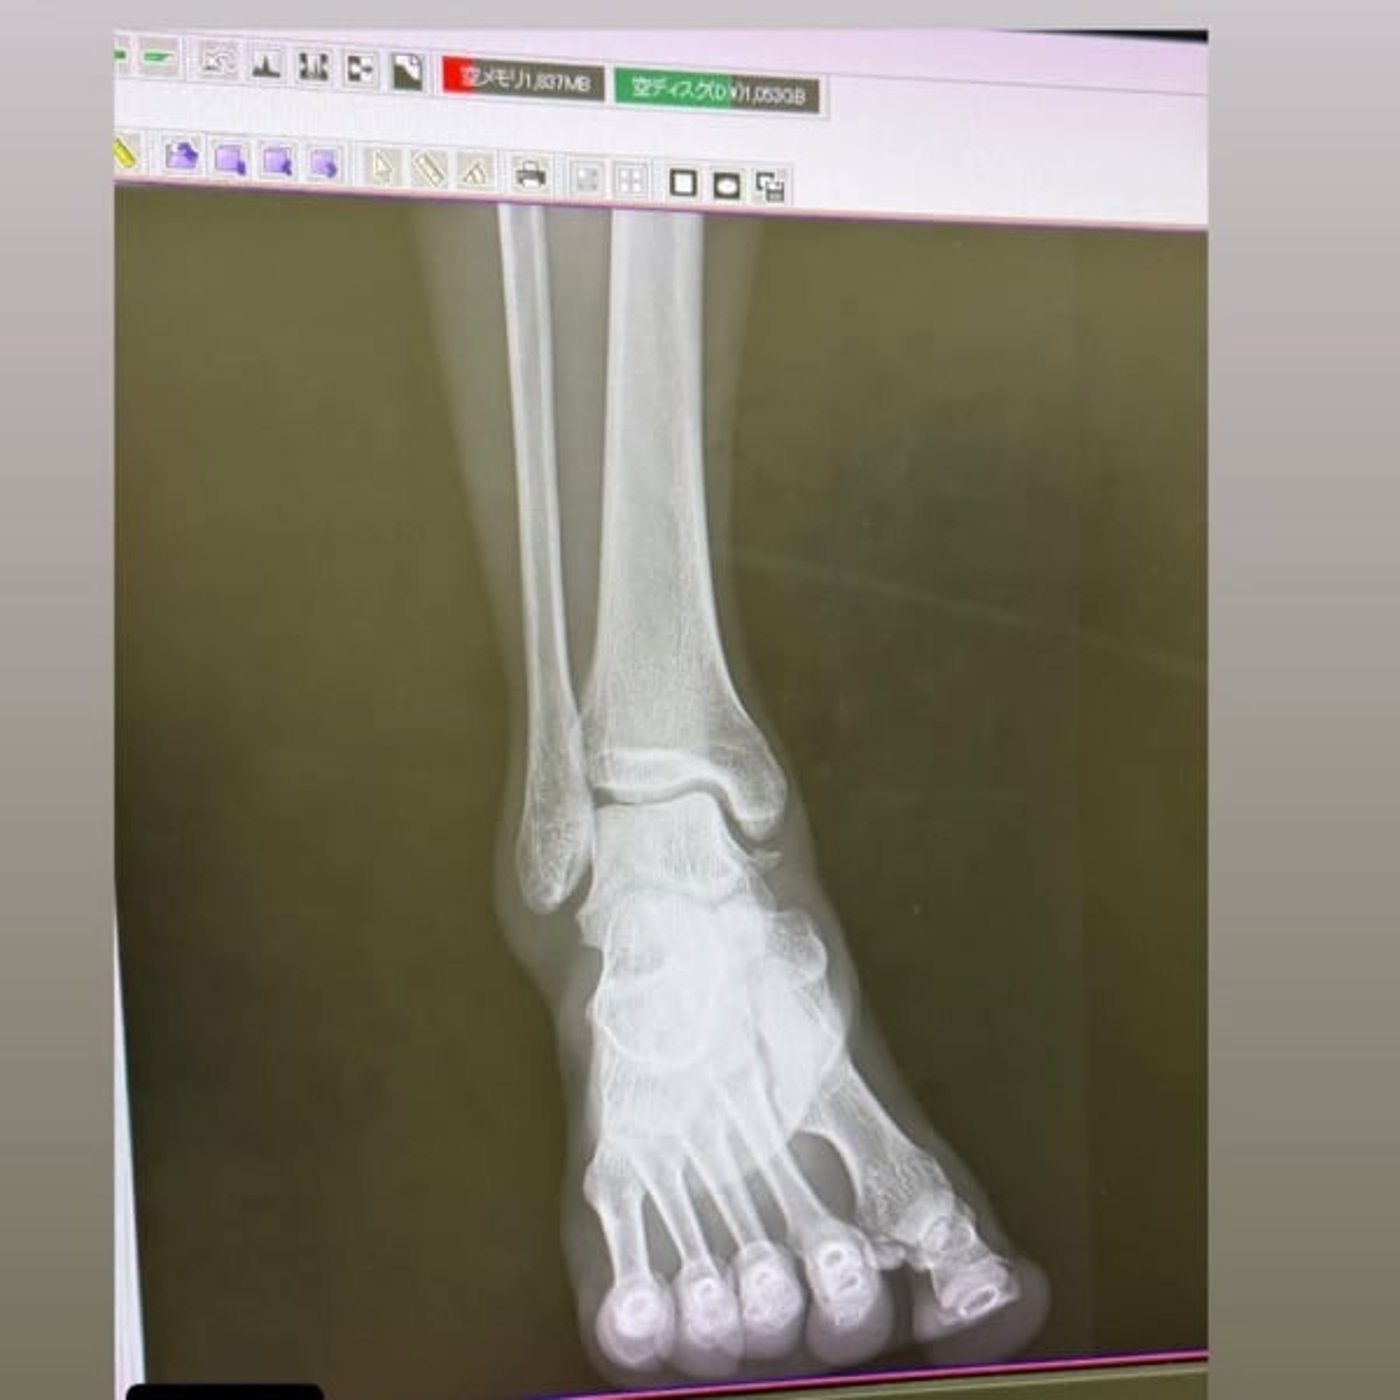

一つ前までのゲストに来てくださったペヤングくんから、ショッキングな画像が届いた!

足首が痛くてレントゲンとエコーを撮った結果!

靭帯全損症、骨が取れている、軟骨損傷…どうも重症みたい。